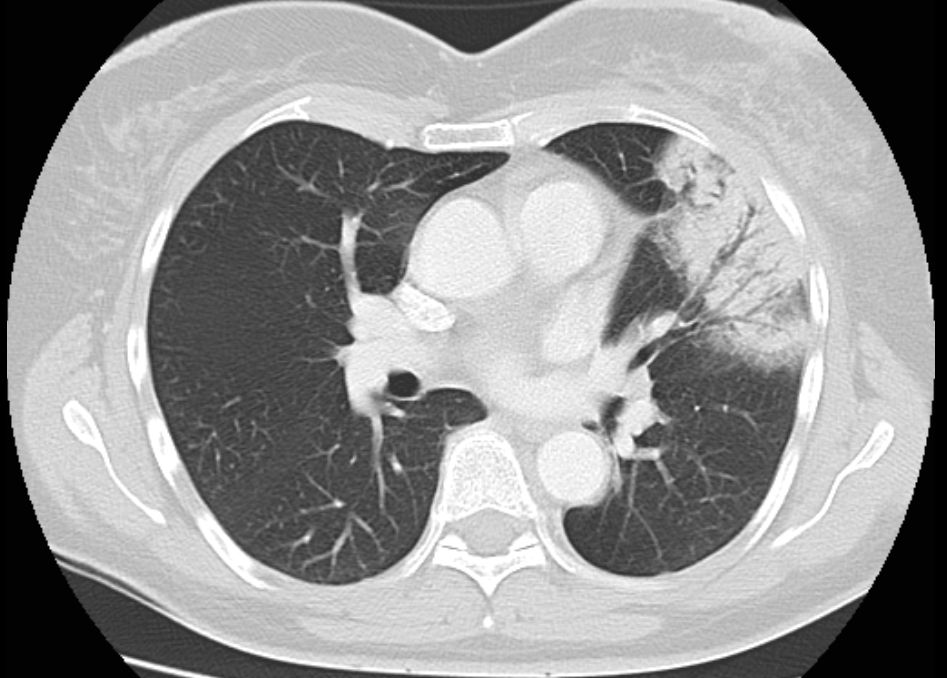

Pneumonitis 53-jährige Frau mit Mammakarzinom links. 3 Monate nach brusterhaltender Therapie und Bestrahlung der Brust wird die Patientin wegen einer Pneumonie ins Krankenhaus eingewiesen. Nach Gabe von Antibiotika zunächst nur geringe Besserung.

Das Thoraxbild zeigt ein Infiltrat im linken Mittelfeld.

Das CT zeigt eine Anschoppung direkt unter der bestrahlten Brust. Negatives Bronchogramm gut erkennbar.

Durch ein leichte Trichterbrust war ungewöhnlich viel Lungenparenchym in der Tangente bestrahlt.